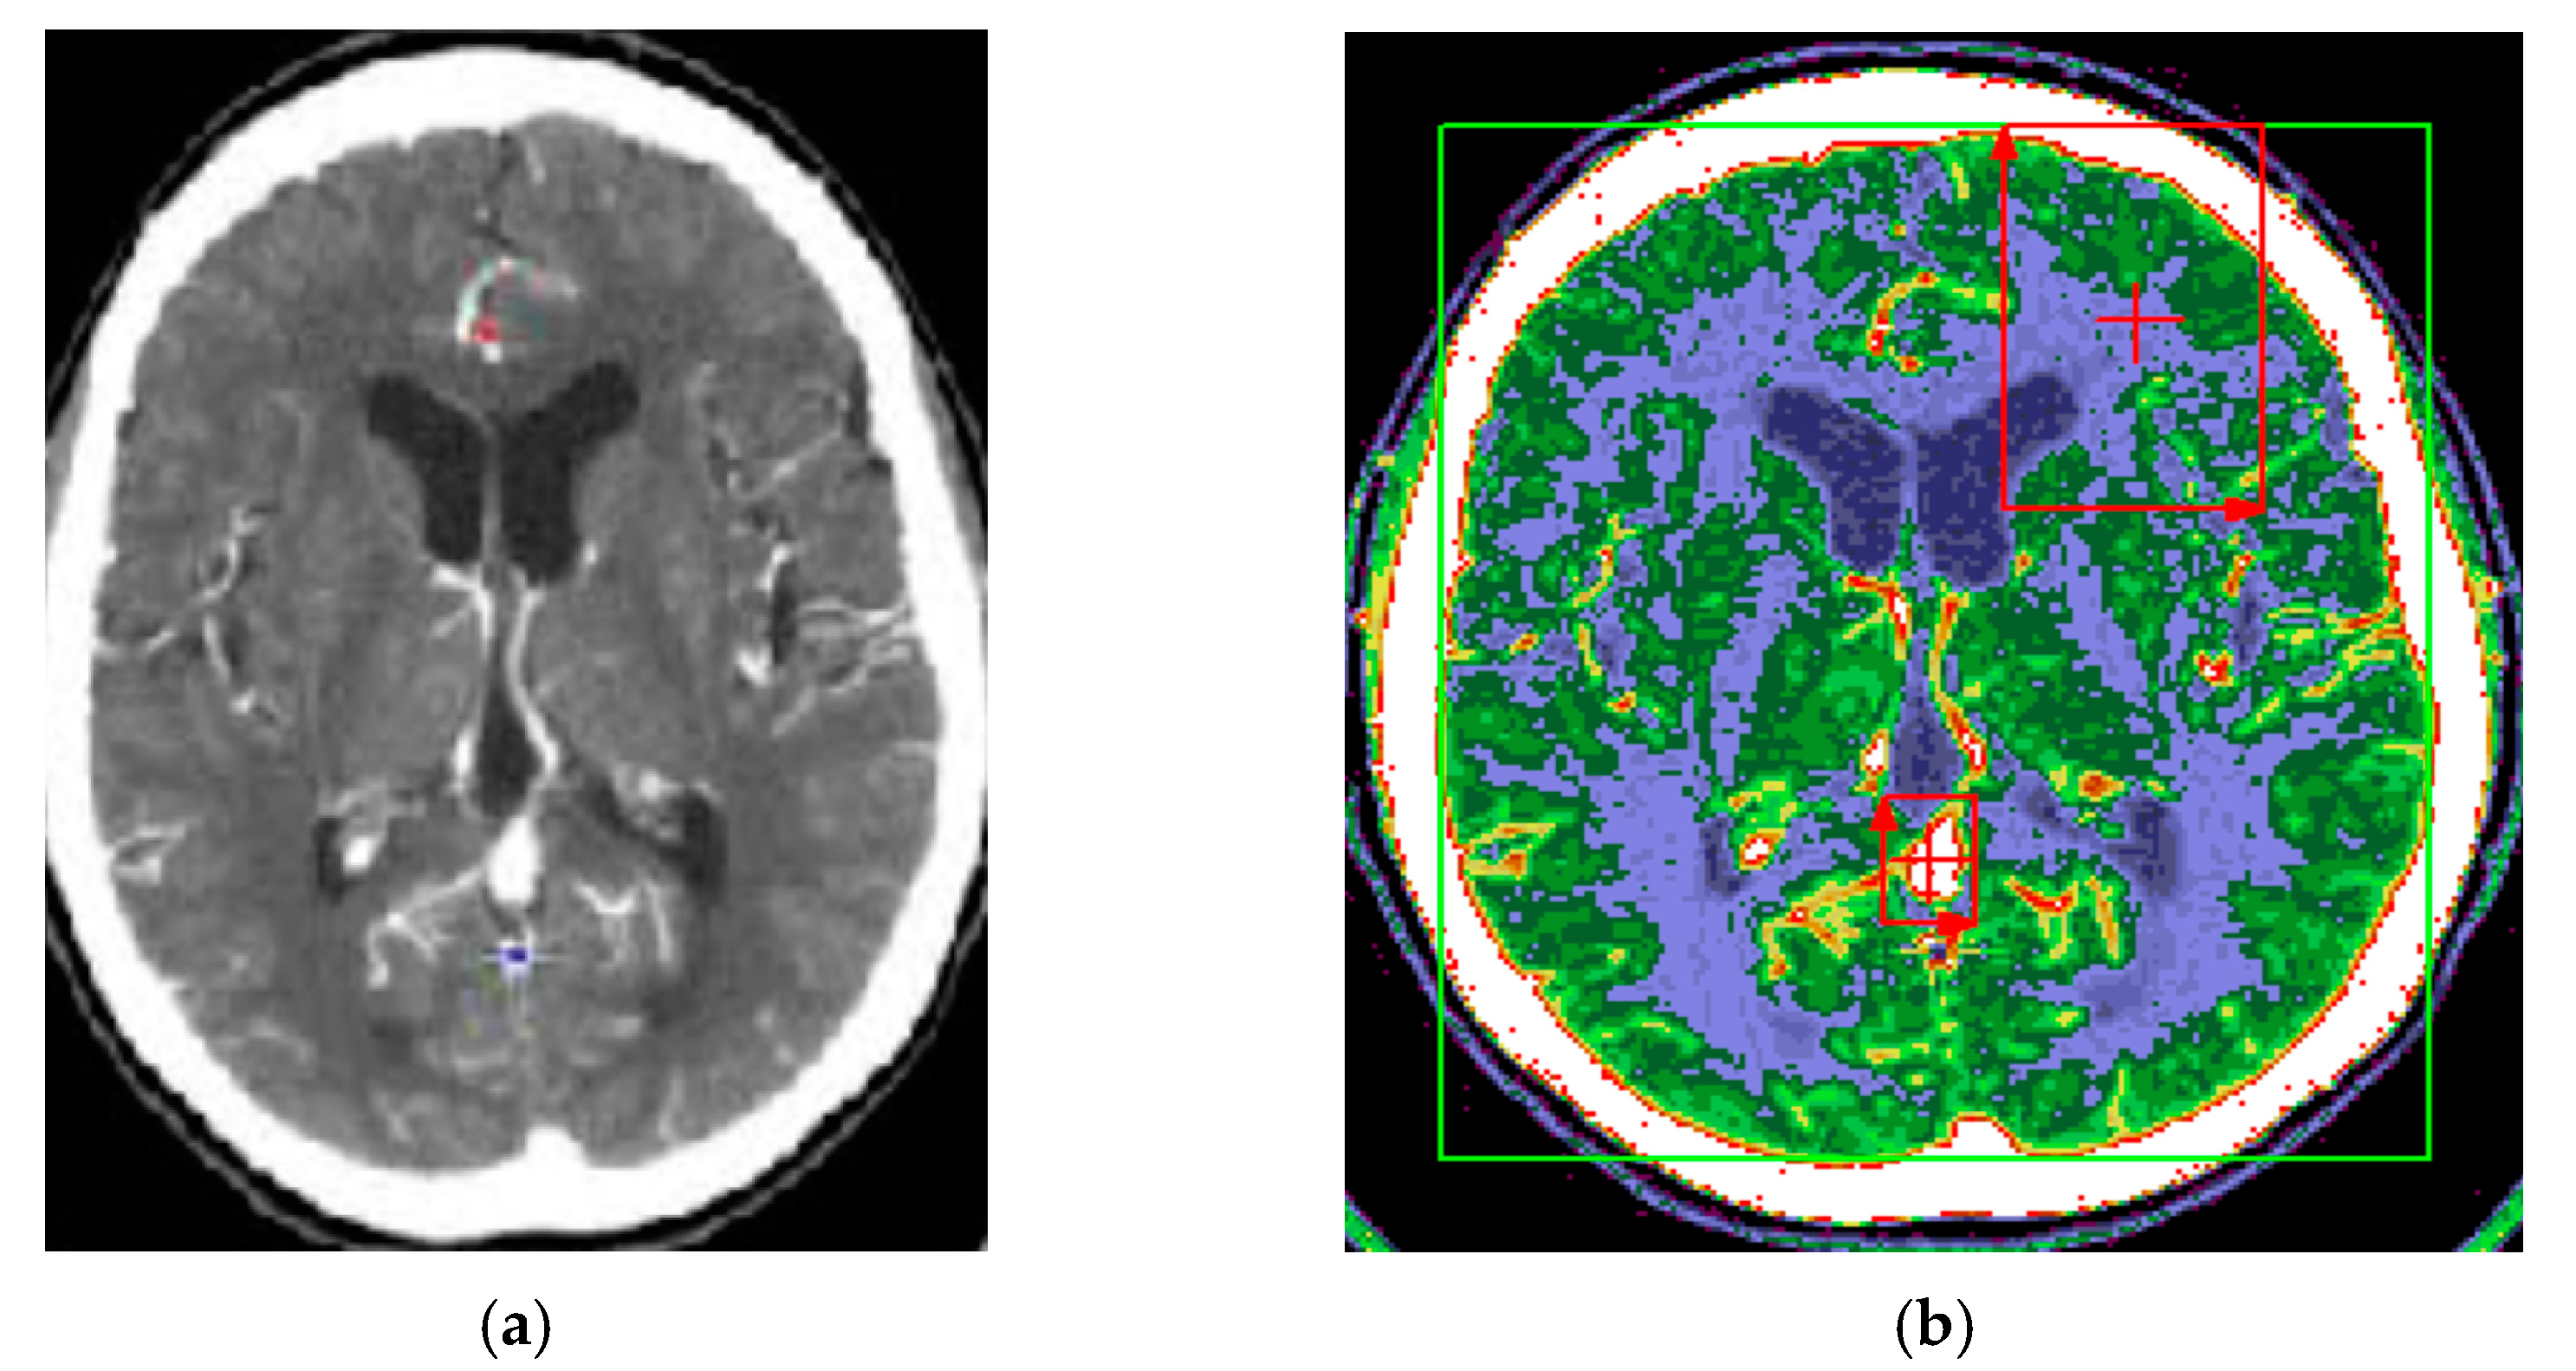

The proposed method for improving images with modified Wiener filter and nonlinear cellular network can be applied with success also with low contrast CT (computer tomograph) images. The improvement of tomographic image quality aims at obtaining superior visibility of the image components, the adaptive increase of the contrast, in order to be interpreted as easily as possible by the specialist doctor. Figure 7, Figure 8 and Figure 9 show the results obtained in the case of such images.

Figure 7. (a) Initial image with low contrast; (b) improved image—CT cranial layer image processed with modified Wiener filter.